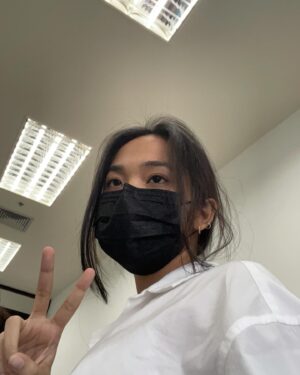

456.9K Likes – Danupha Khanatheerakul Instagram

Caption : สวัสดีค้าบ ส่งท้ายปีเก่าด้วยการ เป็นซีสต์ที่เส้นเสียง เย้ อ่าว ไม่ใช่ แฮะๆ หลังจากที่ใช้เสียงอยากต่อเนื่องไม่พักผ่อนนั้น มินก็เกิดอาหารคอแดงคอบวม (ซึ่งเป็นปกตินะฮะ เราพักผ่อนน้อยเองด้วย) เลยตัดสินใจไปตรวจที่โรงพยาบาลเฉพาะทาง และพบว่าตัวเป็น ซีสต์ที่เส้นเสียงข้างซ้ายข้างเดียว คือจะตัดออกก็ได้หรือจะปล่อยไว้ให้มันแตกเอง แต่มันก็อาจจะไม่แตกเองก็ได้ nobody knows คับ ถ้าผ่า โทนเสียงก็อาจจะเปลี่ยน แต่จริงๆคุณหมอบอกว่าไอ้ซีสต์นี้นวยก็น่าจะมีมาได้สักพักใหญ่ๆแล้วเนื่องจากโทนเสียงของนวยเปลี่ยนไปแล้วรอบนึง คือทุ้มต่ำลง ใช้เวลาตัดสินใจไป1สัปดาห์ ว่าจะผ่าตัดเอามันออก คือขึ้นชื่อว่าซีสต์ ตรงที่เส้นเสียงมันไม่ใช่ที่ที่มันควรอยู่อยู่แล้วอ่ะเนอะ ความจึ้งเกินอยู่ที่ว่า ก่อนหมอจะรมยาสลบ หนูสลบก่อนแล้ว กูหลับเบิ๊ดด หมอต้องปลุกมาดมยาสลบ55555 เลิศต่อมาคือ พอหมอสอดกล้องจะผ่าเอาอีก้อนออก ปรากฎว่า มัน already แตก แบบห๊ะ แบบร่างกายมัน heal ตัวเองไปแล้ว ซึ่งเป็นเรื่องดีนะคะ55555 เท่ากับว่าเราจะหายไวขึ้น ใช้เวลาพักฟื้นน้อยลง คุณหมอว่า โอกาสที่ซีสต์จะเองนี่ไม่ง่ายเลย แต่ก็ดีแล้วค่ะ หลังจากนั้นคือห้ามพูด สามวัน แต่ว่าอยากเล่าเรื่องราวให้พี่ๆฟังเลยส่งไปแบบคลิปสุดท้าย 5555555 สุดท้ายนี้ใครๆก็เป็นซีสต์ได้ รักษาเนื้อรักษาตัวไว้ด้วยนะคะทุกท่าน ปีนี้คงไม่ได้เจอกันในคอนแล้ว แต่อาจจะได้เจอมิลลิตามวัดหรือสถานที่สนุกๆนะคะ อิอิ เบิ้บบูทุกคนมากๆ ปีหน้าเจอกันใหม่ เสียงใสอย่างกับนกไนติงเกลค่ะ เสมอมาเสมอไป 🫶🏽✨Likes : 456898

456.9K Likes – Danupha Khanatheerakul Instagram

Caption : สวัสดีค้าบ ส่งท้ายปีเก่าด้วยการ เป็นซีสต์ที่เส้นเสียง เย้ อ่าว ไม่ใช่ แฮะๆ หลังจากที่ใช้เสียงอยากต่อเนื่องไม่พักผ่อนนั้น มินก็เกิดอาหารคอแดงคอบวม (ซึ่งเป็นปกตินะฮะ เราพักผ่อนน้อยเองด้วย) เลยตัดสินใจไปตรวจที่โรงพยาบาลเฉพาะทาง และพบว่าตัวเป็น ซีสต์ที่เส้นเสียงข้างซ้ายข้างเดียว คือจะตัดออกก็ได้หรือจะปล่อยไว้ให้มันแตกเอง แต่มันก็อาจจะไม่แตกเองก็ได้ nobody knows คับ ถ้าผ่า โทนเสียงก็อาจจะเปลี่ยน แต่จริงๆคุณหมอบอกว่าไอ้ซีสต์นี้นวยก็น่าจะมีมาได้สักพักใหญ่ๆแล้วเนื่องจากโทนเสียงของนวยเปลี่ยนไปแล้วรอบนึง คือทุ้มต่ำลง ใช้เวลาตัดสินใจไป1สัปดาห์ ว่าจะผ่าตัดเอามันออก คือขึ้นชื่อว่าซีสต์ ตรงที่เส้นเสียงมันไม่ใช่ที่ที่มันควรอยู่อยู่แล้วอ่ะเนอะ ความจึ้งเกินอยู่ที่ว่า ก่อนหมอจะรมยาสลบ หนูสลบก่อนแล้ว กูหลับเบิ๊ดด หมอต้องปลุกมาดมยาสลบ55555 เลิศต่อมาคือ พอหมอสอดกล้องจะผ่าเอาอีก้อนออก ปรากฎว่า มัน already แตก แบบห๊ะ แบบร่างกายมัน heal ตัวเองไปแล้ว ซึ่งเป็นเรื่องดีนะคะ55555 เท่ากับว่าเราจะหายไวขึ้น ใช้เวลาพักฟื้นน้อยลง คุณหมอว่า โอกาสที่ซีสต์จะเองนี่ไม่ง่ายเลย แต่ก็ดีแล้วค่ะ หลังจากนั้นคือห้ามพูด สามวัน แต่ว่าอยากเล่าเรื่องราวให้พี่ๆฟังเลยส่งไปแบบคลิปสุดท้าย 5555555 สุดท้ายนี้ใครๆก็เป็นซีสต์ได้ รักษาเนื้อรักษาตัวไว้ด้วยนะคะทุกท่าน ปีนี้คงไม่ได้เจอกันในคอนแล้ว แต่อาจจะได้เจอมิลลิตามวัดหรือสถานที่สนุกๆนะคะ อิอิ เบิ้บบูทุกคนมากๆ ปีหน้าเจอกันใหม่ เสียงใสอย่างกับนกไนติงเกลค่ะ เสมอมาเสมอไป 🫶🏽✨Likes : 456898

456.9K Likes – Danupha Khanatheerakul Instagram

Caption : สวัสดีค้าบ ส่งท้ายปีเก่าด้วยการ เป็นซีสต์ที่เส้นเสียง เย้ อ่าว ไม่ใช่ แฮะๆ หลังจากที่ใช้เสียงอยากต่อเนื่องไม่พักผ่อนนั้น มินก็เกิดอาหารคอแดงคอบวม (ซึ่งเป็นปกตินะฮะ เราพักผ่อนน้อยเองด้วย) เลยตัดสินใจไปตรวจที่โรงพยาบาลเฉพาะทาง และพบว่าตัวเป็น ซีสต์ที่เส้นเสียงข้างซ้ายข้างเดียว คือจะตัดออกก็ได้หรือจะปล่อยไว้ให้มันแตกเอง แต่มันก็อาจจะไม่แตกเองก็ได้ nobody knows คับ ถ้าผ่า โทนเสียงก็อาจจะเปลี่ยน แต่จริงๆคุณหมอบอกว่าไอ้ซีสต์นี้นวยก็น่าจะมีมาได้สักพักใหญ่ๆแล้วเนื่องจากโทนเสียงของนวยเปลี่ยนไปแล้วรอบนึง คือทุ้มต่ำลง ใช้เวลาตัดสินใจไป1สัปดาห์ ว่าจะผ่าตัดเอามันออก คือขึ้นชื่อว่าซีสต์ ตรงที่เส้นเสียงมันไม่ใช่ที่ที่มันควรอยู่อยู่แล้วอ่ะเนอะ ความจึ้งเกินอยู่ที่ว่า ก่อนหมอจะรมยาสลบ หนูสลบก่อนแล้ว กูหลับเบิ๊ดด หมอต้องปลุกมาดมยาสลบ55555 เลิศต่อมาคือ พอหมอสอดกล้องจะผ่าเอาอีก้อนออก ปรากฎว่า มัน already แตก แบบห๊ะ แบบร่างกายมัน heal ตัวเองไปแล้ว ซึ่งเป็นเรื่องดีนะคะ55555 เท่ากับว่าเราจะหายไวขึ้น ใช้เวลาพักฟื้นน้อยลง คุณหมอว่า โอกาสที่ซีสต์จะเองนี่ไม่ง่ายเลย แต่ก็ดีแล้วค่ะ หลังจากนั้นคือห้ามพูด สามวัน แต่ว่าอยากเล่าเรื่องราวให้พี่ๆฟังเลยส่งไปแบบคลิปสุดท้าย 5555555 สุดท้ายนี้ใครๆก็เป็นซีสต์ได้ รักษาเนื้อรักษาตัวไว้ด้วยนะคะทุกท่าน ปีนี้คงไม่ได้เจอกันในคอนแล้ว แต่อาจจะได้เจอมิลลิตามวัดหรือสถานที่สนุกๆนะคะ อิอิ เบิ้บบูทุกคนมากๆ ปีหน้าเจอกันใหม่ เสียงใสอย่างกับนกไนติงเกลค่ะ เสมอมาเสมอไป 🫶🏽✨Likes : 456898

456.9K Likes – Danupha Khanatheerakul Instagram

Caption : สวัสดีค้าบ ส่งท้ายปีเก่าด้วยการ เป็นซีสต์ที่เส้นเสียง เย้ อ่าว ไม่ใช่ แฮะๆ หลังจากที่ใช้เสียงอยากต่อเนื่องไม่พักผ่อนนั้น มินก็เกิดอาหารคอแดงคอบวม (ซึ่งเป็นปกตินะฮะ เราพักผ่อนน้อยเองด้วย) เลยตัดสินใจไปตรวจที่โรงพยาบาลเฉพาะทาง และพบว่าตัวเป็น ซีสต์ที่เส้นเสียงข้างซ้ายข้างเดียว คือจะตัดออกก็ได้หรือจะปล่อยไว้ให้มันแตกเอง แต่มันก็อาจจะไม่แตกเองก็ได้ nobody knows คับ ถ้าผ่า โทนเสียงก็อาจจะเปลี่ยน แต่จริงๆคุณหมอบอกว่าไอ้ซีสต์นี้นวยก็น่าจะมีมาได้สักพักใหญ่ๆแล้วเนื่องจากโทนเสียงของนวยเปลี่ยนไปแล้วรอบนึง คือทุ้มต่ำลง ใช้เวลาตัดสินใจไป1สัปดาห์ ว่าจะผ่าตัดเอามันออก คือขึ้นชื่อว่าซีสต์ ตรงที่เส้นเสียงมันไม่ใช่ที่ที่มันควรอยู่อยู่แล้วอ่ะเนอะ ความจึ้งเกินอยู่ที่ว่า ก่อนหมอจะรมยาสลบ หนูสลบก่อนแล้ว กูหลับเบิ๊ดด หมอต้องปลุกมาดมยาสลบ55555 เลิศต่อมาคือ พอหมอสอดกล้องจะผ่าเอาอีก้อนออก ปรากฎว่า มัน already แตก แบบห๊ะ แบบร่างกายมัน heal ตัวเองไปแล้ว ซึ่งเป็นเรื่องดีนะคะ55555 เท่ากับว่าเราจะหายไวขึ้น ใช้เวลาพักฟื้นน้อยลง คุณหมอว่า โอกาสที่ซีสต์จะเองนี่ไม่ง่ายเลย แต่ก็ดีแล้วค่ะ หลังจากนั้นคือห้ามพูด สามวัน แต่ว่าอยากเล่าเรื่องราวให้พี่ๆฟังเลยส่งไปแบบคลิปสุดท้าย 5555555 สุดท้ายนี้ใครๆก็เป็นซีสต์ได้ รักษาเนื้อรักษาตัวไว้ด้วยนะคะทุกท่าน ปีนี้คงไม่ได้เจอกันในคอนแล้ว แต่อาจจะได้เจอมิลลิตามวัดหรือสถานที่สนุกๆนะคะ อิอิ เบิ้บบูทุกคนมากๆ ปีหน้าเจอกันใหม่ เสียงใสอย่างกับนกไนติงเกลค่ะ เสมอมาเสมอไป 🫶🏽✨Likes : 456898